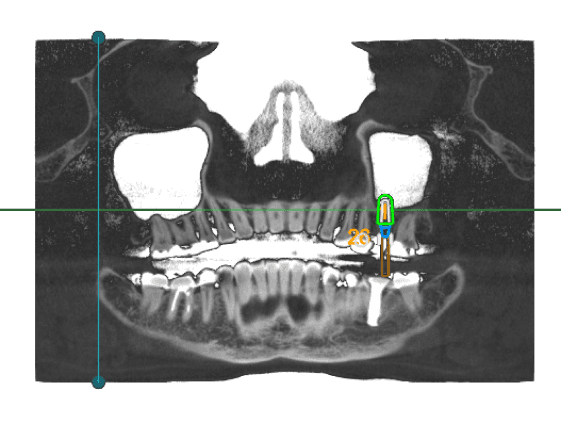

Nerve Detection & Live Safety Zone

Every nerve traced. Every margin measured. Every movement validated in real time.

Automatic mandibular canal tracing in seconds.

AI highlights safety margins dynamically as implants move.

Instant collision alerts for nerve or bone proximity.

Displays minimum clearance and color-coded validation.